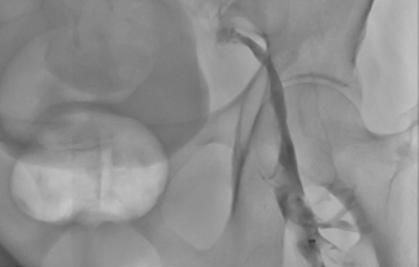

患者,女,73岁,于入院前3天无出现左下肢肿胀;伴酸困、肢体冰凉,患者未予重视,未行任何诊治。此后左下肢肿胀进行性加重,伴活动明显受限。在外院查下肢静脉彩超示:左侧髂外、股总、股深(分出段)、股浅上中段、肌间静脉血栓形成。于2025.02.12以“1.下肢静脉血栓形成 2.髂静脉压迫综合征”就诊于心内介入科,入院后行“下腔静脉滤器置入+下肢静脉置管溶栓术”,术后给予“肝素钠注射液”抗凝,“注射用尿激酶 (40万) 静脉泵入 2次/天”溶栓;经溶栓治疗后复查下肢静脉造影提示血栓负荷明显减轻,遂行髂静脉支架植入术,术后继续利伐沙班抗凝治疗。

下肢静脉造影 术中抽出血栓